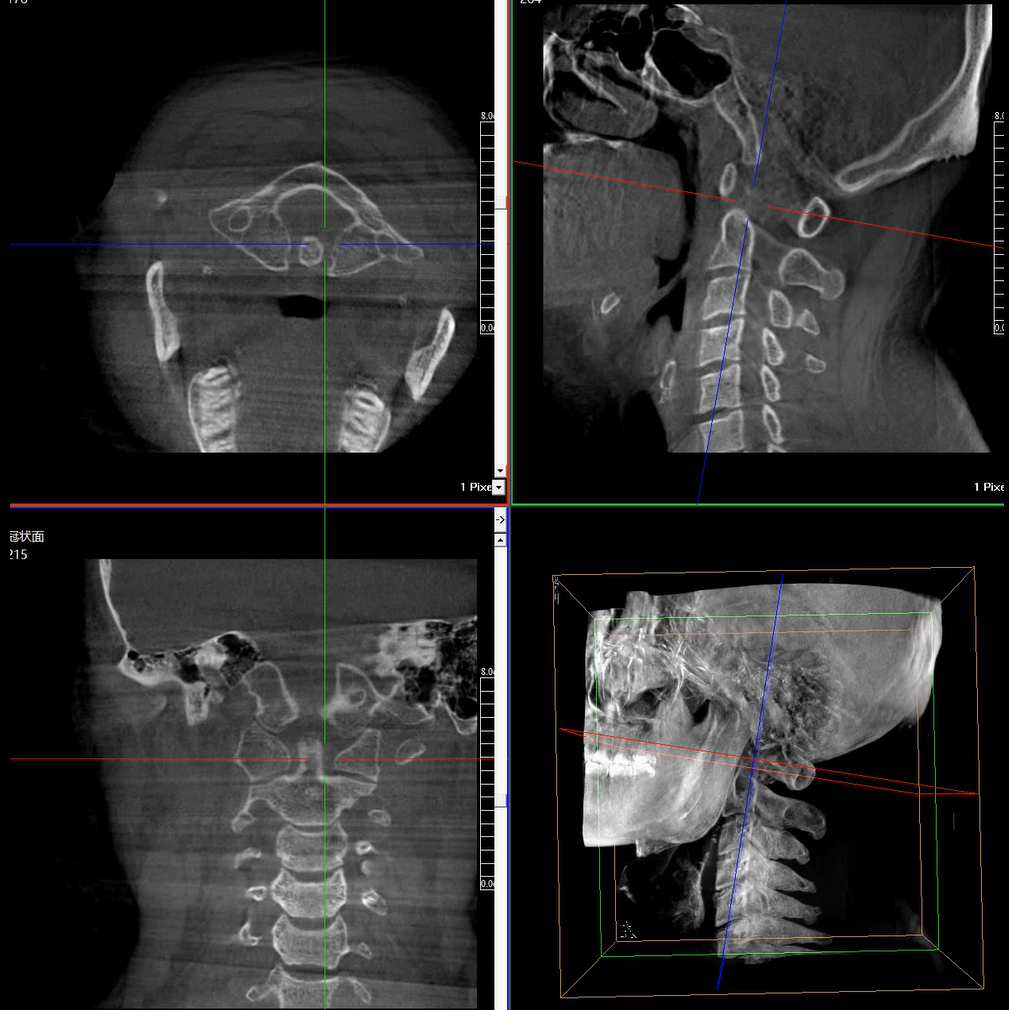

提供更大的術(shù)中三維成像視野,采集更多圖像信息,可一次拍全全段頸椎、全段腰椎、七節(jié)胸椎、雙側(cè)骶髂關(guān)節(jié)、股骨頭及單側(cè)盆骨。

在C臂掃描過(guò)程中,始終保持拍攝主體處于射線束的中心,避免了序列圖像采集過(guò)程中的橫縱方向運(yùn)動(dòng),減少相對(duì)運(yùn)動(dòng)造成的運(yùn)動(dòng)偽影。